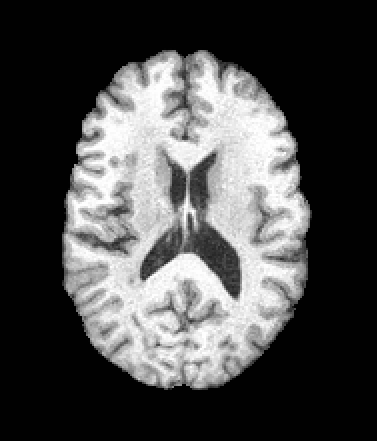

A trained MetaVoxel model can be unconditionally sampled by drawing Gaussian or categorical noise for each variable at timestep , and iteratively apply the denoising network until reaching . Unlike conventional diffusion models that focus solely on image generation, MetaVoxel can generate coherent synthetic patient profiles from the joint distribution , as shown in Figure 2.

| Age: 64.0 | Age: 53.8 | Age: 70.9 | Age: 76.9 |

| Sex: Male | Sex: Female | Sex: Female | Sex: Male |

![]() |

| Age: 80.9 | Age: 77.7 | Age: 73.2 | Age: 84.6 |

| Sex: Male | Sex: Female | Sex: Female | Sex: Female |